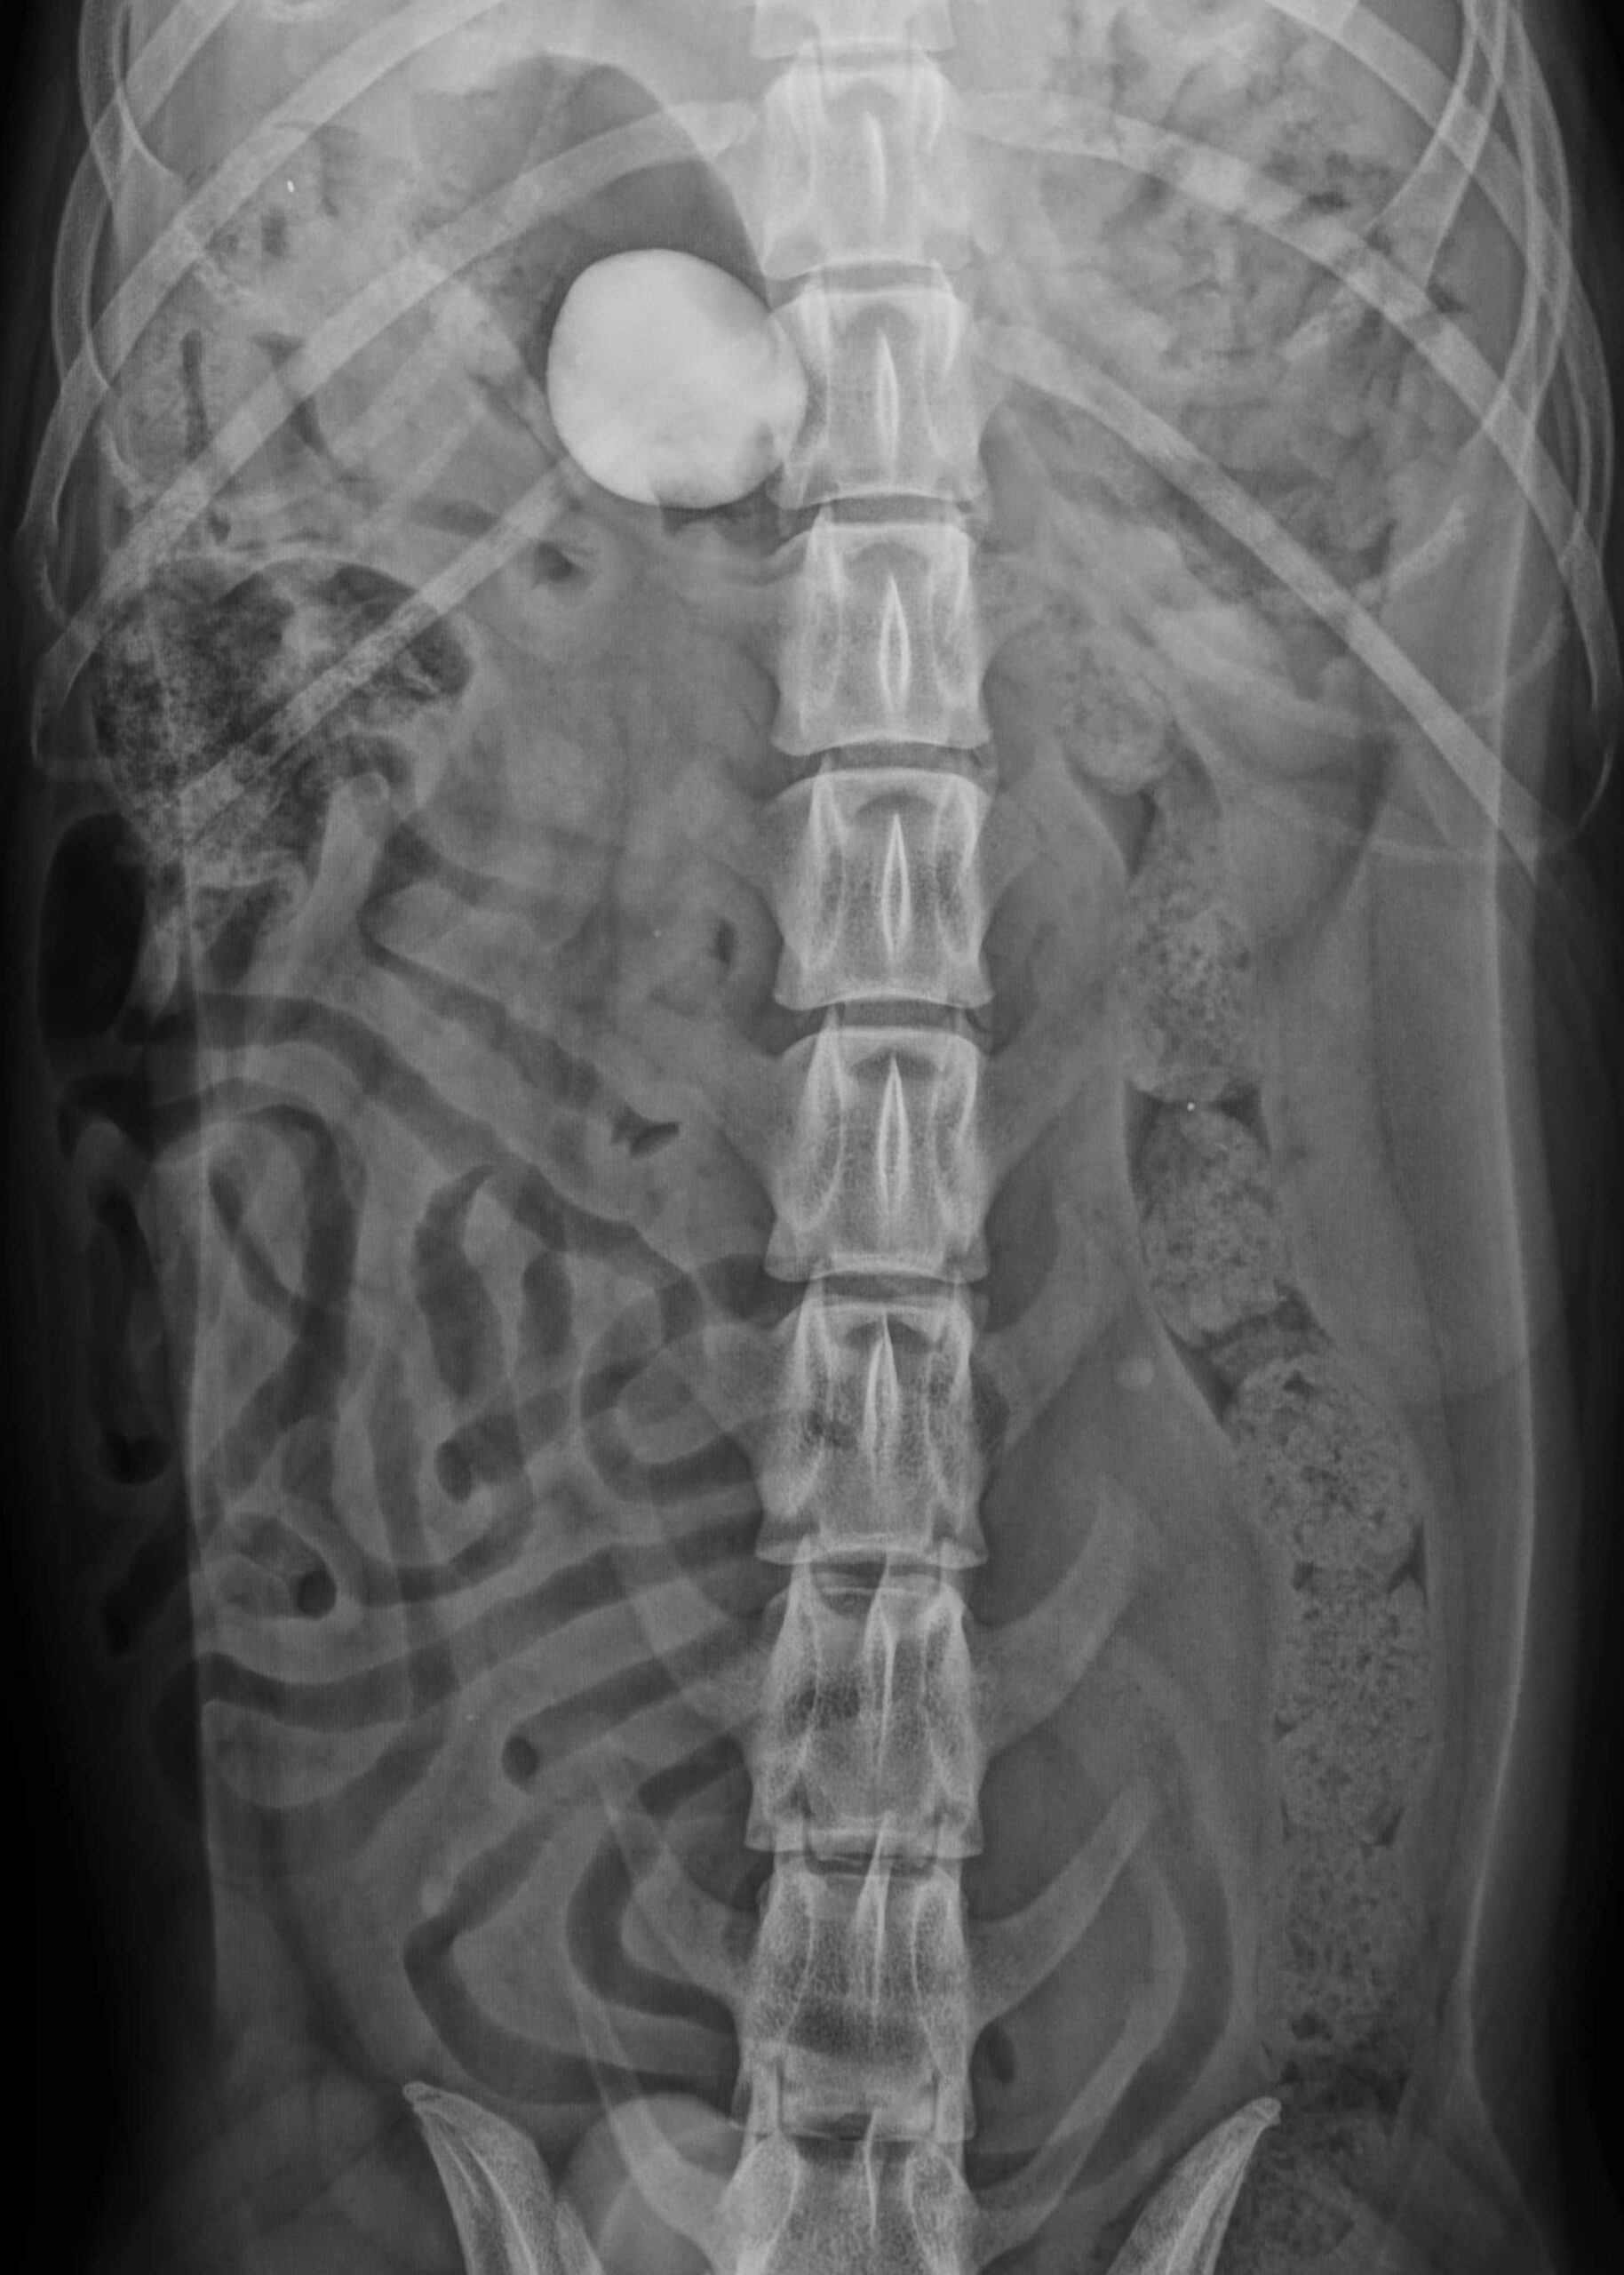

„Der Hund war gestresst und schwer zu untersuchen, aufgrund des stark angespannten Bauches war das Abtasten kaum möglich. Rio hatte eine leicht erhöhte Temperatur, ansonsten war er klinisch unauffällig. Umso wichtiger war die bildgebende Diagnostik. Das Röntgenbild zeigte eine deutlich röntgendichte Struktur, also einen Fremdkörper im Magen-Darmbereich“, beschreibt die behandelnde Tierärztin Dr. Helene Stübing.

Da zunächst unklar war, ob sich der Fremdkörper – vermutlich der verschwundene Stein – noch im Magen oder schon bereits im Darm befand, wurde ein spezielles Kontrastmittelverfahren angewendet.

Dabei wurde dem Tier unter Narkose Luft rektal verabreicht, um die Darmschlingen für eine genauere Beurteilung der Lage des Fremdkörpers aufzublähen. Die anschließende Bildgebung im Röntgen ergab einen starken Hinweis darauf, dass sich der Fremdkörper noch im Magen befindet.

Auf beiden Röntgenbildern gut zu sehen: Der verschluckte Stein.